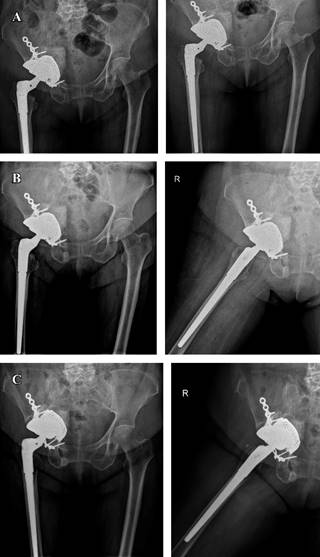

Se coloca copa acetabular no cementada Cupule Quattro 50 milímetros de Zimmer Biomet y se verifica estabilidad. Subsecuentemente, se realiza fresado de canal femoral y colocación de cemento óseo previo a inserción de vástago femoral de revisión tipo Arcos 13 × 150 milímetros más cono proximal de Zimmer Biomet. Finalmente, se coloca cabeza femoral de 28 milímetros doble movilidad par de fricción metal polietileno de Grupe Lepine (Genay, Francia).

Se realiza reducción de componentes protésicos y verificación de adecuada estabilidad. Síntesis de diéresis y control radiográfico postquirúrgico (Figura 6).

Figura 6: Control radiográfico postquirúrgico inmediato.